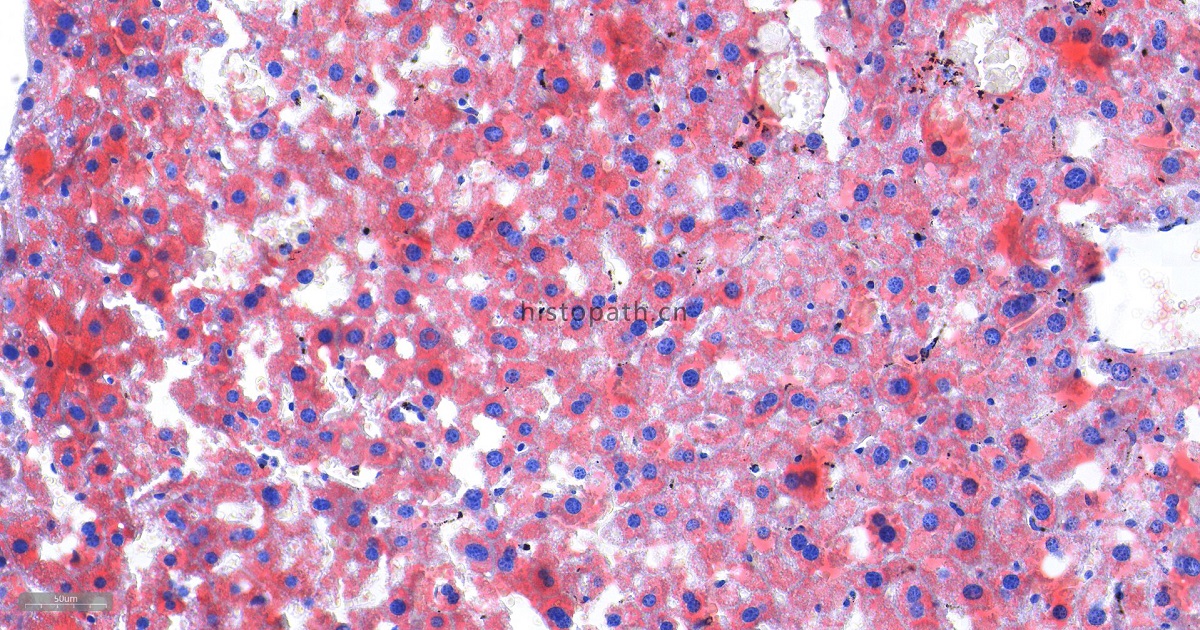

苏丹Ⅲ染色原理:

脂类包括脂肪和类脂,根据其性质可分为中性脂肪、脂肪酸、胆固醇、磷脂及其他类脂质。中性脂类包括甘油三酯、胆固醇、类固醇及糖酯等。酸性脂类包括脂肪酸和磷脂等。各种脂肪与类脂质在体内都是混合存在的。体脂主要为中性脂肪。类脂的功能为与蛋白质、糖类结合构成细胞的基本成分。脂质的共同物理性质为不溶于水而易溶于乙醇、乙醚、四氯化碳等有机溶剂,因此,选择固定剂是应避免用有机溶剂。脂质理想的固定剂是甲醛钙或10%中性缓冲福尔马林。脂肪染色切片要用冰冻切片。

染色结果分析:中性脂肪呈橙红色,细胞核呈蓝色。